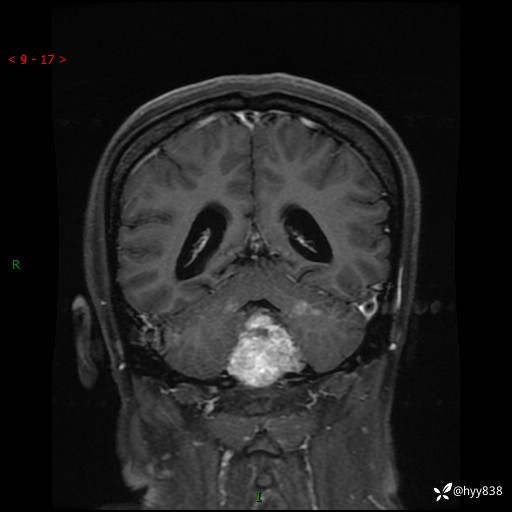

性别:女

年龄:47岁

简要病史:头晕1年余,间断恶心不伴呕吐

颅脑MRI平扫+DWI

增强(axi+cor+sag)

轴内、轴外占位

病灶的影像特征

轴内或轴外肿瘤